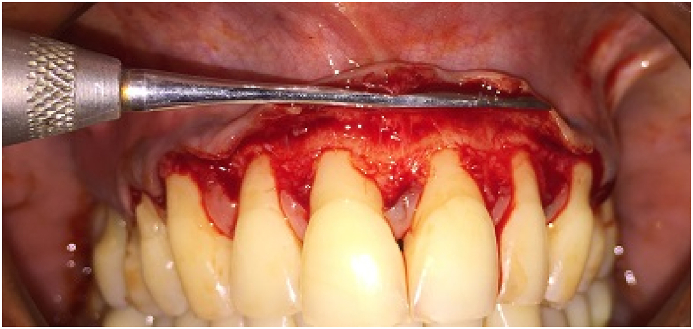

2.7. PPG + CAF (test group)

The patients were treated with a combination of periosteal pedicle graft and coronally advanced flap as illustrated by Mahajan.17 An intrasulcular incision was given on the buccal aspect of each tooth involved with 15C (Swann-Morton Ltd., Sheffield, UK) blade followed by a horizontal right angle incision slightly coronal to the CEJ was placed into the adjacent interdental papilla. This horizontal incision was connected by the vertical incisions which was placed divergent extending from the gingival margin to the alveolar mucosa on the two sides of the last tooth involved (Fig. 1a, Fig. 1b, Fig. 1c). A full thickness flap was raised 3–4 mm apical to the bony dehiscence, from this point apically, partial thickness flap was created by sharp dissection to expose adequate periosteum. The exposed periosteum was slowly separated from the apical end using periosteal elevator (Hu-freidy P-24) from the underlying bone, while care was taken that it remained attached at it coronal most ends. De-epithelisation of the papillae adjacent to the defect was performed.

Full thickness flap reflected 3–4 mm apical to gingival margin and then split thickness flap reflected, exposing the underlying periosteum.